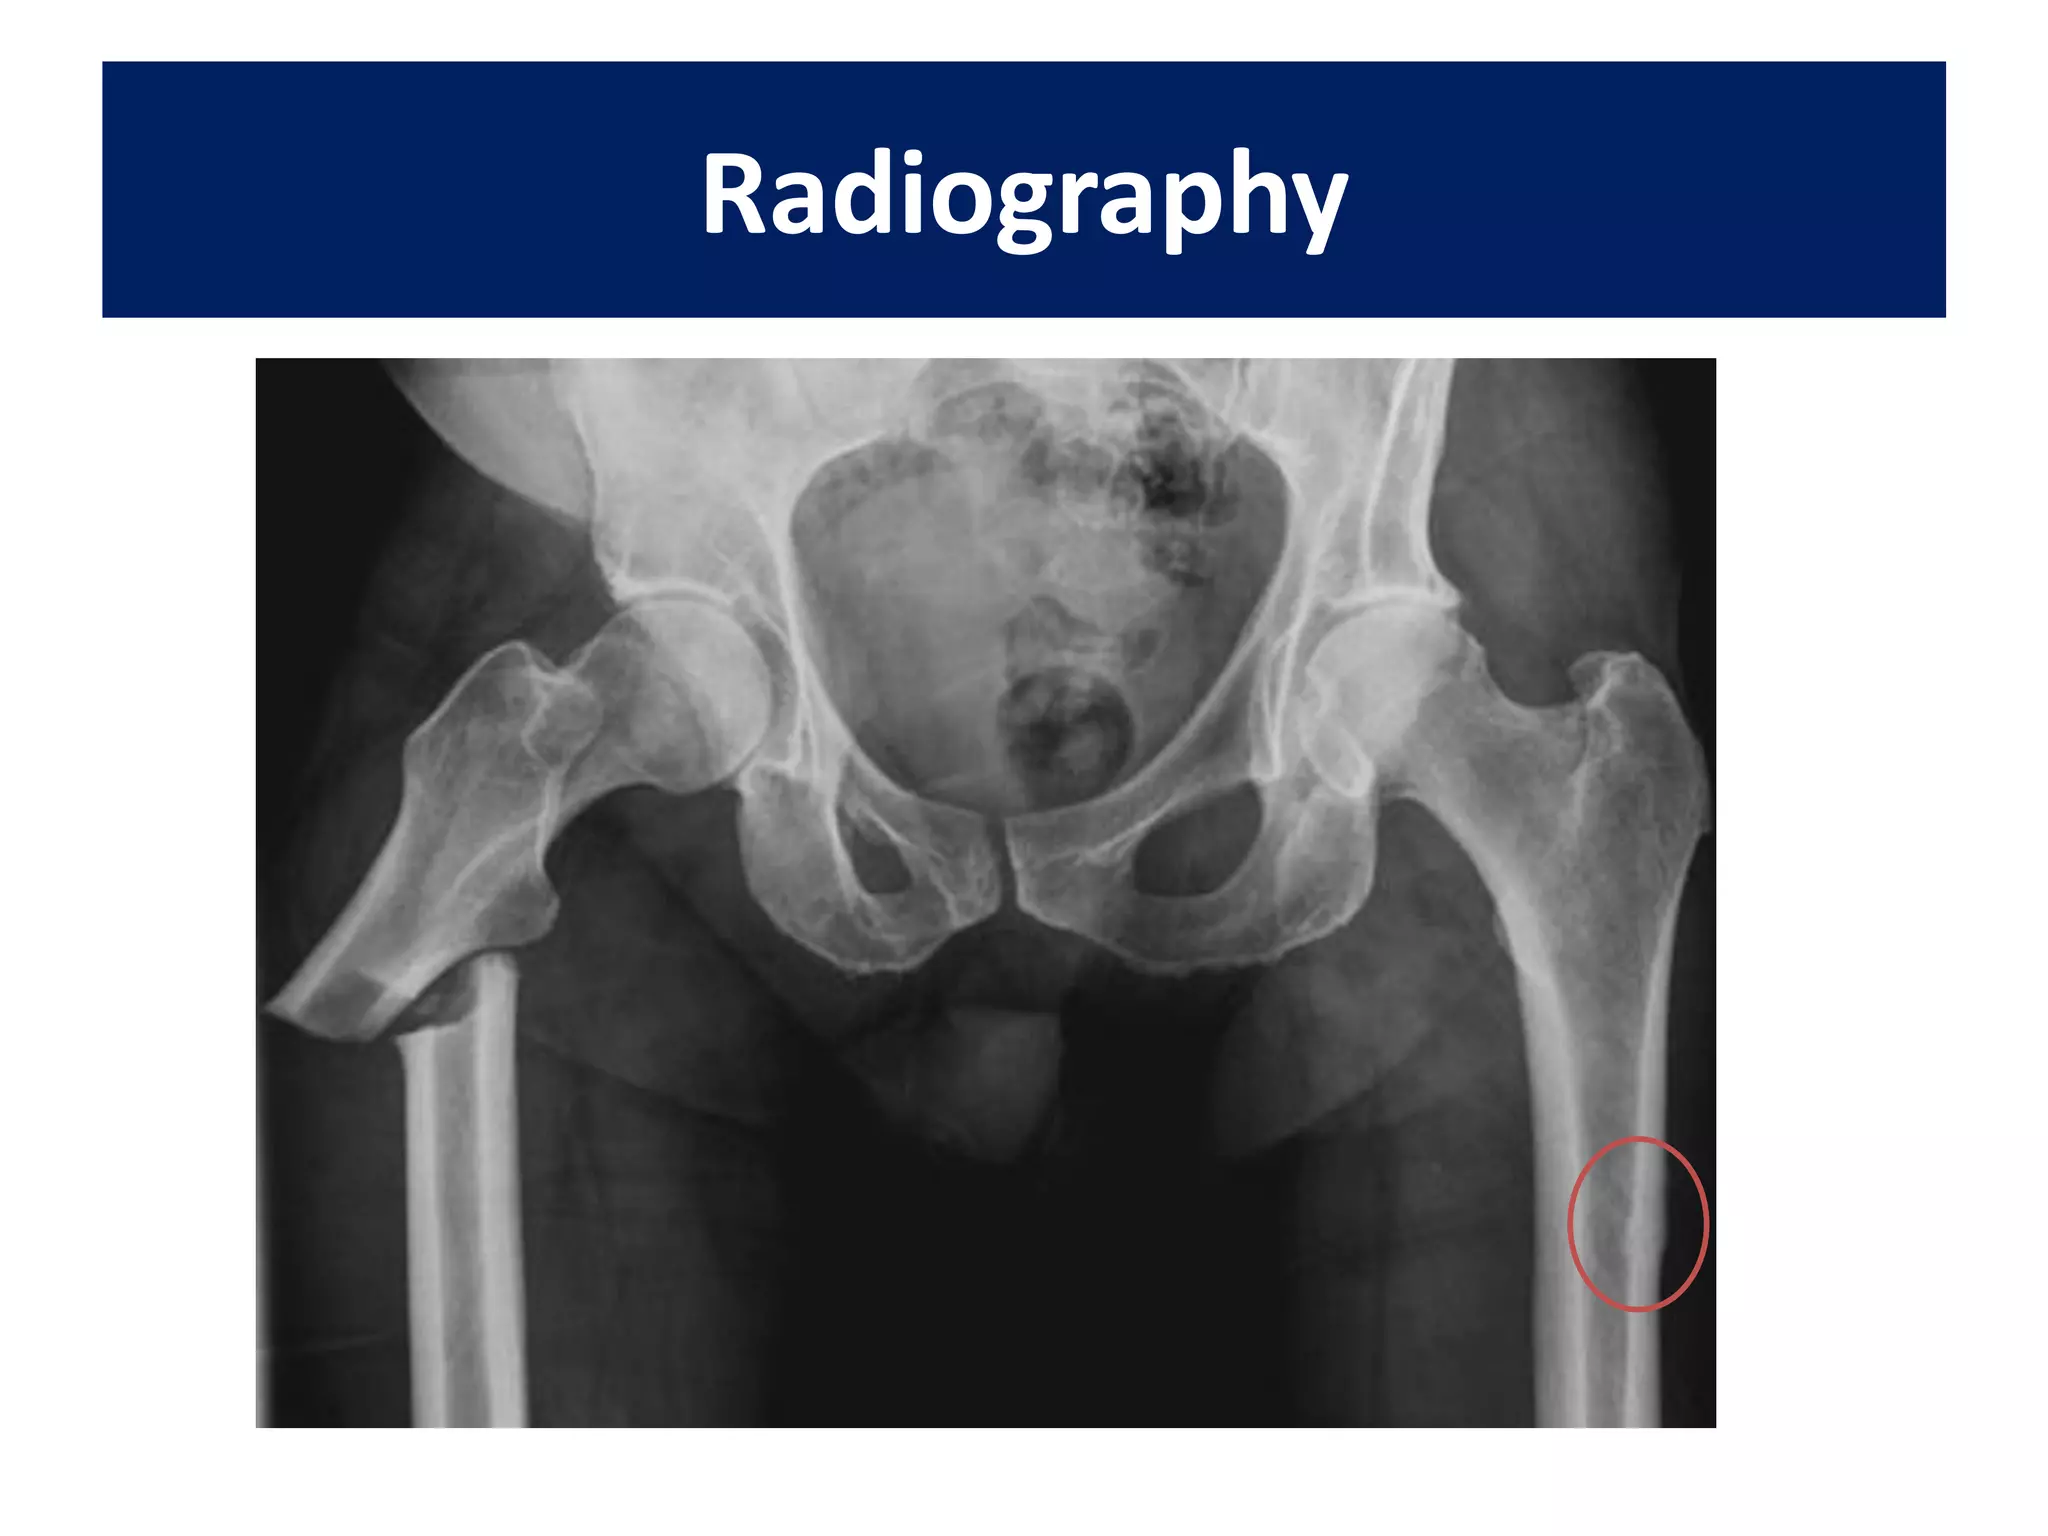

Radiographs should include

• an anteroposterior (AP) view of the pelvis,

• A full length AP and lateral films of the femur

• Traction views.

Radiography